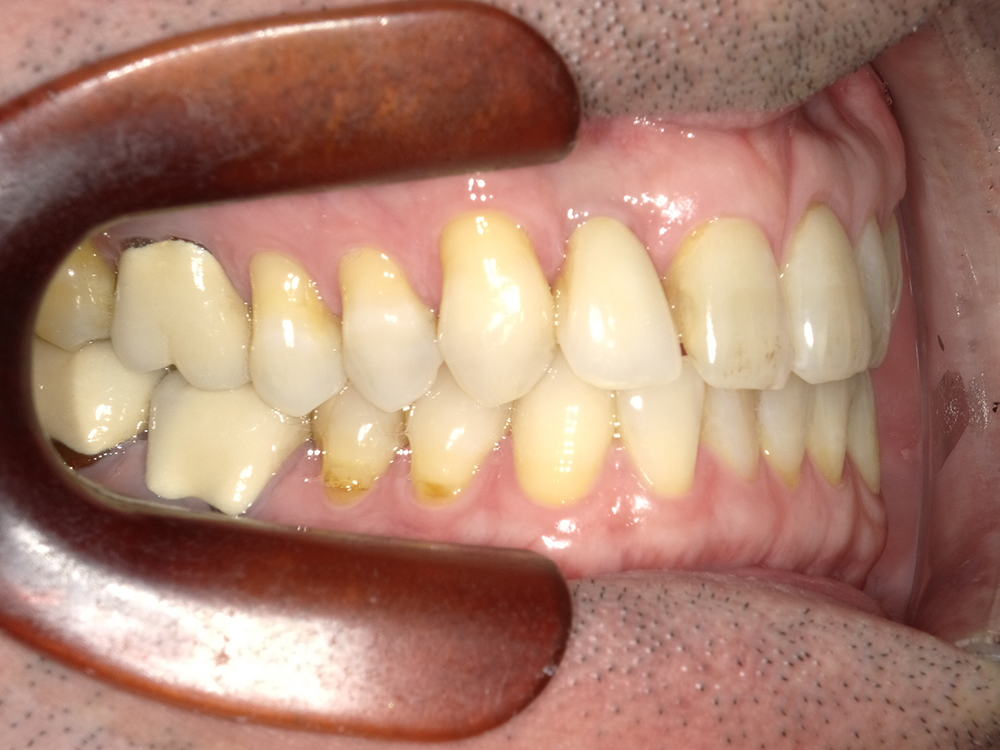

55歳 男性

- 主訴

- 前歯でしか咬めなく、食事を採るのに非常に困難で辛い

- 処置内容

- 上顎6本、下顎3本

- 治療費用

- 上顎:約230万(税込)下顎:約120万(税込)

- 治療期間

- 上顎:1年(仮歯まで8か月)下顎:8か月(仮歯まで5か月)

- リスク

- 上部構造物、仮歯の破折、術後の腫れ(3日)、人工歯根脱落リスクがあります